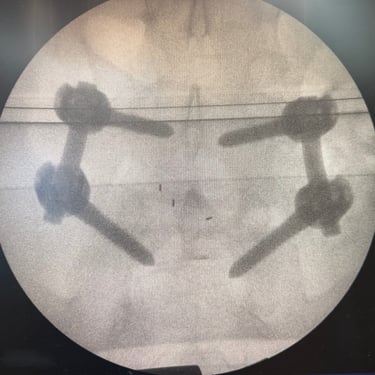

Síndrome Postdiscectomía: Tratamiento con Cirugía TLIF Mínimamente Invasiva

El síndrome postdiscectomía se presenta cuando persiste o reaparece el dolor lumbar y radicular después de una cirugía previa de hernia discal. Puede estar asociado a inestabilidad segmentaria, fibrosis epidural o degeneración discal progresiva. Cuando el manejo conservador no logra aliviar los síntomas, la fusión intersomática transforaminal (TLIF) mínimamente invasiva constituye una alternativa eficaz. Este procedimiento permite descomprimir las estructuras nerviosas, restaurar la altura discal y estabilizar el segmento afectado con menor daño muscular. La técnica mínimamente invasiva favorece menor sangrado, recuperación más rápida y mejores resultados funcionales.